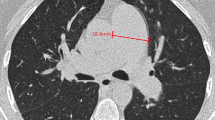

All CTPA images were evaluated by two board-certified radiologists with 11 and 14 years of experience, respectively. Blinding the clinical data was ensured by using a dedicated commercially available diagnostic workstation (Centricity RA 1000, GE Healthcare). The widest short-axis diameter of the main pulmonary artery (dPA) was measured, and the mean of two perpendicular measurements of the ascending aortic diameter (the aortic diameter [dAA]) was calculated using transverse images at the level of the PA bifurcation (Fig. 1a, b); the dPA/dAA ratio was calculated [20, 21]. The widest long-axis diameter of the right atrium (dRA) and the widest short-axis diameters of the right (dRV) and left ventricles (dLV) were also measured on the transverse images (Fig. 1c, d); the dPA/dRA ratio and dRV/dLV ratio were calculated [21]. Diameter of the right ventricular free wall thickness (dRVW) was also measured (Fig. 1c, d) according to previous literature [22]. The measurements of the blood vessel, atrium, and ventricle diameters were performed using the outer limits of the filled contrast medium.

Vascular and cardiac chamber diameter measurements on computed tomography pulmonary angiography images. The widest short-axis diameter of the main pulmonary artery (dPA) is measured, and the mean of two perpendicular measurements of the ascending aortic diameter to represent the aortic diameter (dAA) is calculated using transverse images at the level of the PA bifurcation (orange, blue, and green lines in Fig. 1a, b, respectively). The dPA/dAA ratio is calculated. The widest long-axis diameter of the right atrium (dRA), the widest short-axis diameters of the right and left ventricles (dRV, dLV), and the short-axis diameters of right ventricular free wall thickness (dRVW) are also measured on transverse images (orange, blue, green, and yellow lines in Figs. 1c, d, respectively). The dPA/dRA ratio and dRV/dLV ratio are calculated.